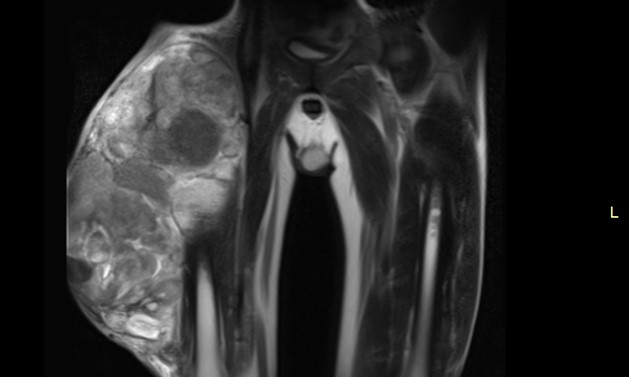

43-летнему пациенту удалили опухоль мягких тканей бедра весом более 7 кг. Образование размером более 30 см имело признаки инвазии в мышцы беда и охватывало сосудисто-нервный пучок бедра на ½.

В 2018 году мужчина обнаружил припухлость на поверхности правого бедра. Выполненное МРТ показало образование размером около 13 см. Но впервые к специалистам Петербургского онкоцентра пациент обратился только в октябре 2019 года с жалобами на постоянный рост опухоли. Гистологический анализ подтвердила диагноз: миксофибросаркома.

На момент операции размер опухоли составлял 17,6х19,9х30,0см. У пациента отмечался распространенный опухолевый процесс. Она прорастала практически во все мышцы бедра, отвечающие за разгибание голени, сдавливала жизненно важные сосуды и нервы. Для удаления опухоли пришлось мобилизовать бедренную артерию и бедренную вену от паховой складки до коленного сустава с выделением бедренного нерва и его ветвей. Операция по удалению опухоли с резекцией латеральной широкой, медиальной широкой, прямой, портняжной мышц бедра длилась 4 часа и прошла успешно с минимальной кровопотерей.